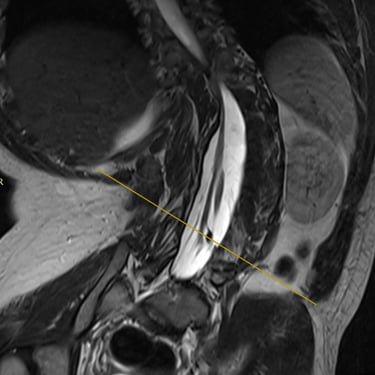

La médula anclada es una condición en la que la médula espinal queda fijada o traccionada anormalmente dentro del canal vertebral, generando síntomas como dolor lumbar, debilidad en las piernas, alteraciones sensitivas y disfunción urinaria. El tratamiento indicado es la liberación quirúrgica, un procedimiento microquirúrgico que busca desprender las adherencias y liberar la médula, permitiendo su movilidad normal. Se realiza con neuronavegación y monitoreo neurofisiológico para proteger las estructuras nerviosas. Esta cirugía, cuando se realiza oportunamente, detiene la progresión del daño neurológico y mejora la función motora y sensitiva del paciente.